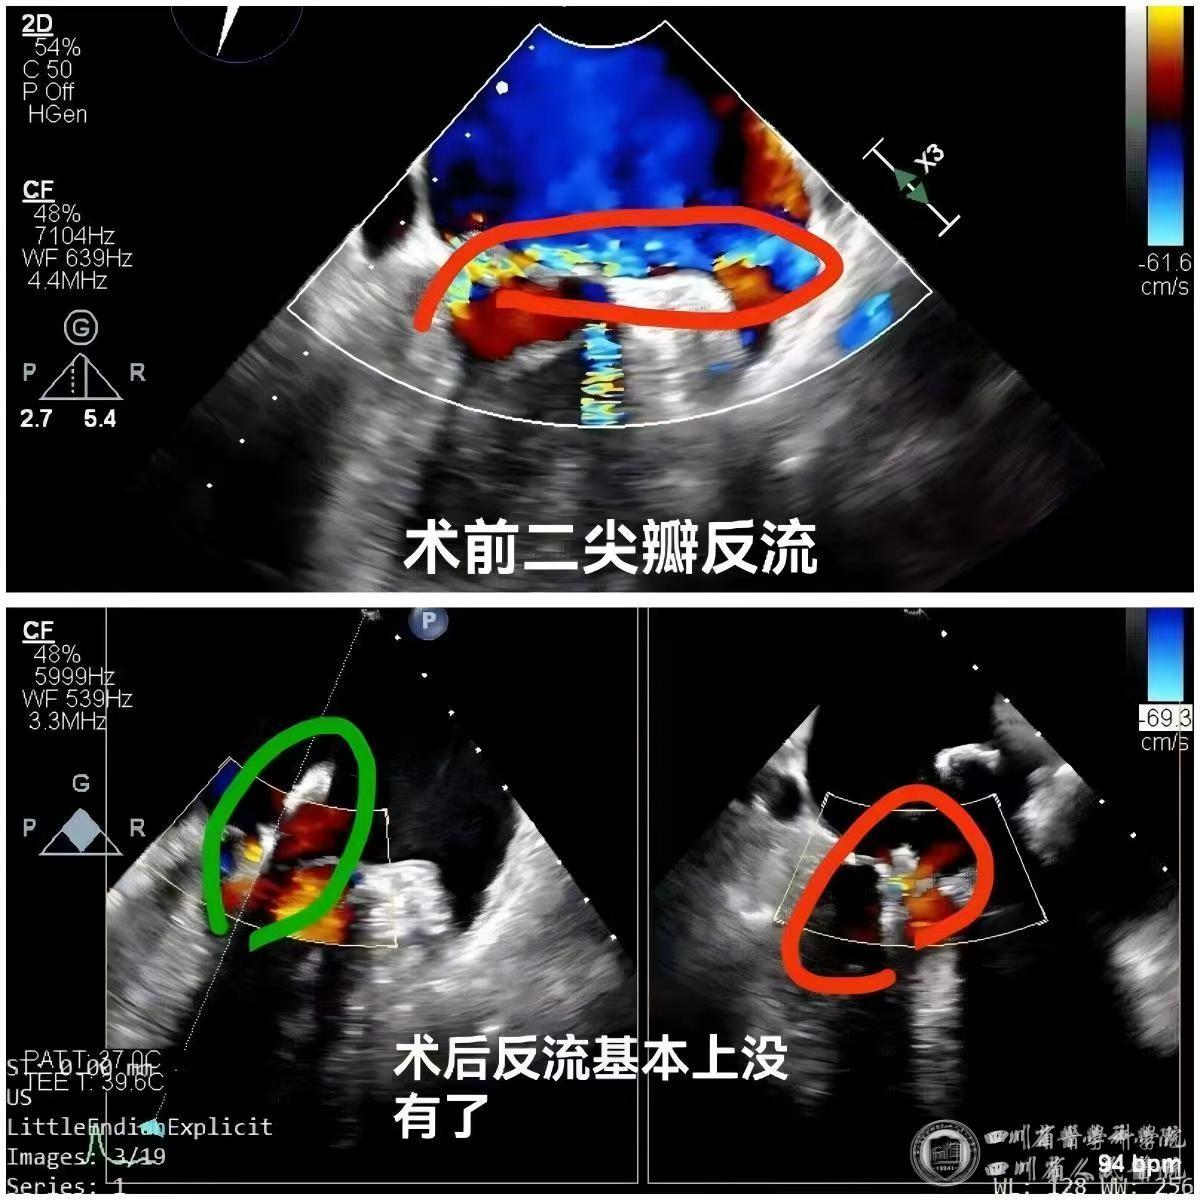

近日,我院心脏外科中心完成一例高难度经导管二尖瓣缘对缘修复手术(TEER术)。该例手术的顺利完成,标志着我院在复杂心脏瓣膜病微创治疗领域达到川内领先水平。

患者张婆婆为老年女性,确诊原发性重度二尖瓣反流,伴腱索断裂脱入左心房14mm,还合并肥厚型梗阻性心肌病典型“SAM征(Systolic Anterior Motion,指在超声心动图检查中,二尖瓣前叶在收缩期向室间隔方向异常前移的波形现象,常见于梗阻性肥厚型心肌病)”,左心室流出道梗阻,存在胸闷、猝死等极高风险,属复杂危重病例。

心脏外科于涛团队与患者、家属充分沟通后,经麻醉科、心血管超声及心功能科多学科会诊,结合患者高龄、病情复杂的特点,决定采用全程零射线、纯超声引导的经导管二尖瓣缘对缘修复(TEER)微创手术方案。3月7日,术者于涛主任医师、向波副主任医师、魏大闯主治医师在麻醉科吕强主任医师和心血管超声及心功能科左明良主任医师、李文华副主任医师的协作下,为患者施行了该高难度微创手术。无影灯下,术者以经食道超声精准导航,从患者大腿静脉血管送入介入器械,精准定位病变区域并完成瓣叶夹合,手术历时3小时,术中患者生命体征一直保持稳定。术后第二天,患者即可下床活动。